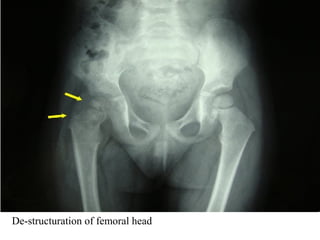

TB hip

Uniform narrowing

of left hip joint due

to synovial disease

(white arrowhead)

Osteporosis of left

hip

No osteophytes and

no sclerosis

Normal right hip

joint

De-structuration of femoral head

TB hip Uniform narrowing ofleft hip joint due to synovial disease (white arrowhead) Osteporosis of left hip No osteophytes and no sclerosis Normal right hip joint